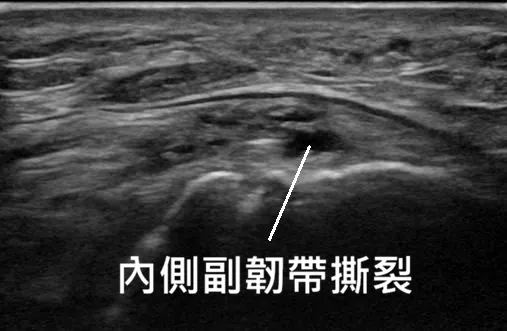

🔍 超音波檢查:眼見為憑的診斷

X 光只能看骨頭,診斷副韌帶損傷,超音波是第一線利器。宸新復健科採用高階超音波檢查:

1.副韌帶結構檢查

高階超音波影像可以清楚看到副韌帶的結構,撕裂的程度,並搭配超音波導引精準注射效果更好。